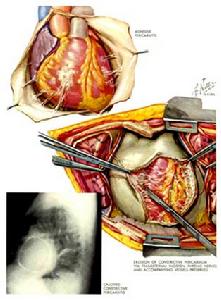

一旦細菌性心包炎的診斷成立,除全身使用足量的抗生素外,仍應立即施行心包切開術因為全身抗生素治療及向心包腔內注入抗生素皆不能防止腔內膿液的形成.甚至可因大量心包積液而引起心臟壓塞,或因包裹性積膿形成而發展成縮窄性心包炎對於有些稠厚的化膿性積液形成連小腔需做廣泛的心包切開術達到充分引流以預防發生縮窄性心包炎。根據心包積液性質及血培養的結果或藥物敏感試驗選用敏感的抗生素必要時需多種抗生素聯合使用。抗生素的劑量須大療程應充分,在感染控制後仍需維持2周。

細菌性心包炎風濕性心包炎時應加強抗風濕治療,一筋骨和腎上腺皮質激素較好;結核性心包炎時應遲早開始抗結核治療,並給予足夠的劑量和較長的療程,直到結核活動停止後一年左右再停藥,如出現心臟壓塞症狀,應進行心包穿刺放液;如滲液繼續產生或有心包縮窄表現,應及時作心包切除,以防止發展為縮窄性心包炎;化膿性心包炎時應選用足量對致病菌有效的抗生素,並反覆心包穿刺抽膿和心包腔內注入抗生素,如療效不著,即應及早考慮心包切開引流,如引流發現心包增厚,則可作廣泛心包切除;非特異性心包炎時腎上腺皮質激素可能有效,如反覆發作亦可考慮心包切除。